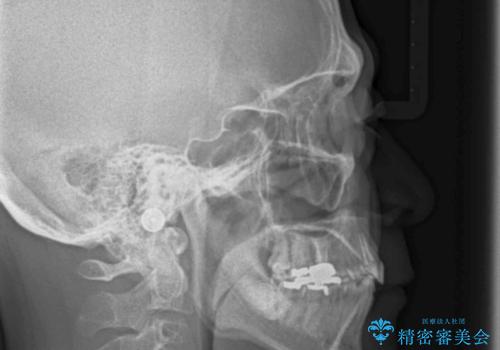

小臼歯の歯根長が長いことを治療前にレントゲンで確認し抜歯部位を決定しました。